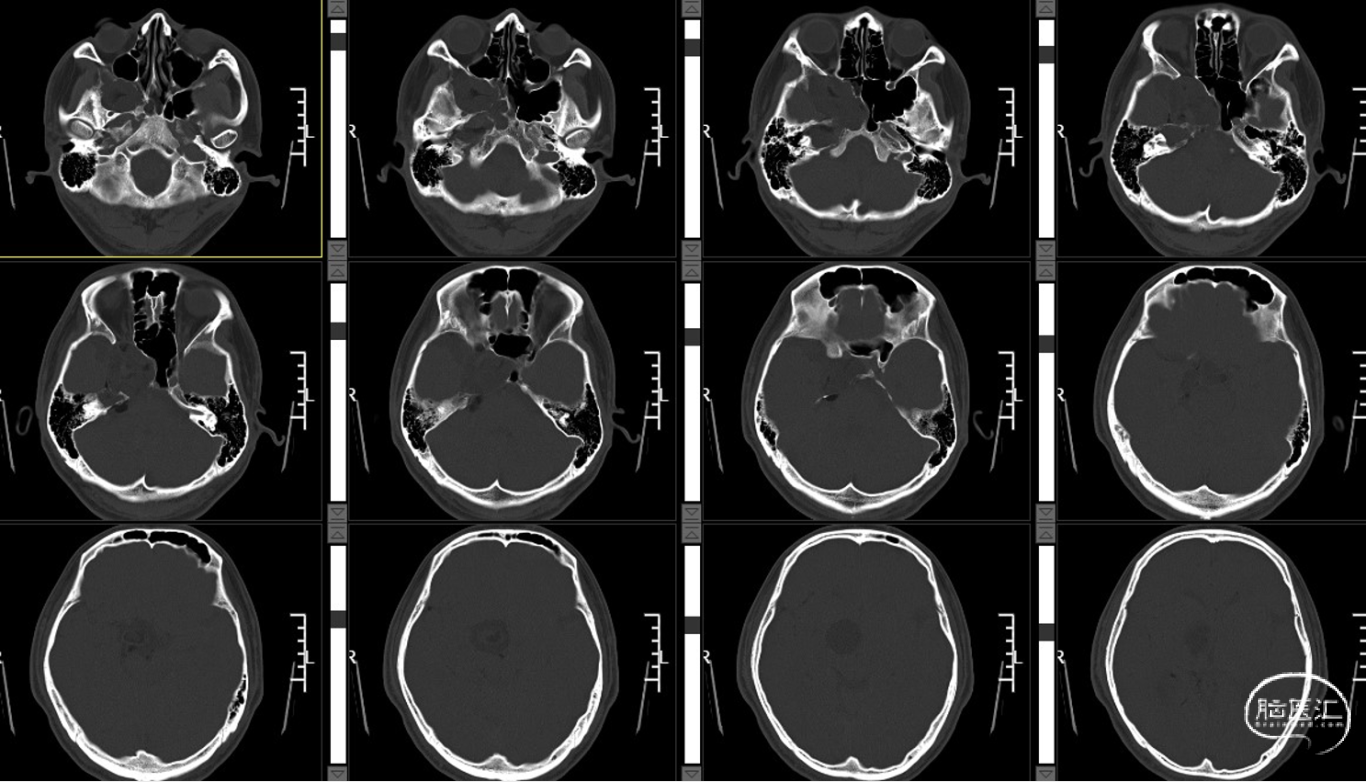

外院CT示:右侧颅底占位性病变,临近骨质部分吸收。